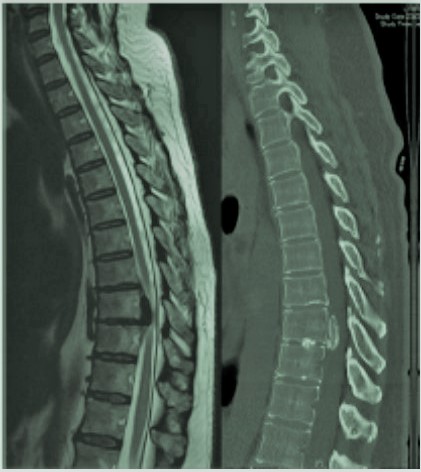

Mucho menos frecuentes que las hernias discales lumbares y cervicales. Asocian generalmente dorsalgia no irradiada. La mayoría mejora con tratamiento conservador. Sin embargo, en caso de que generen compresión a nivel de la médula espinal pueden dar lugar a un cuadro de mielopatía con ataxia de la marcha y paraparesia espástica precisando intervención quirúrgica.